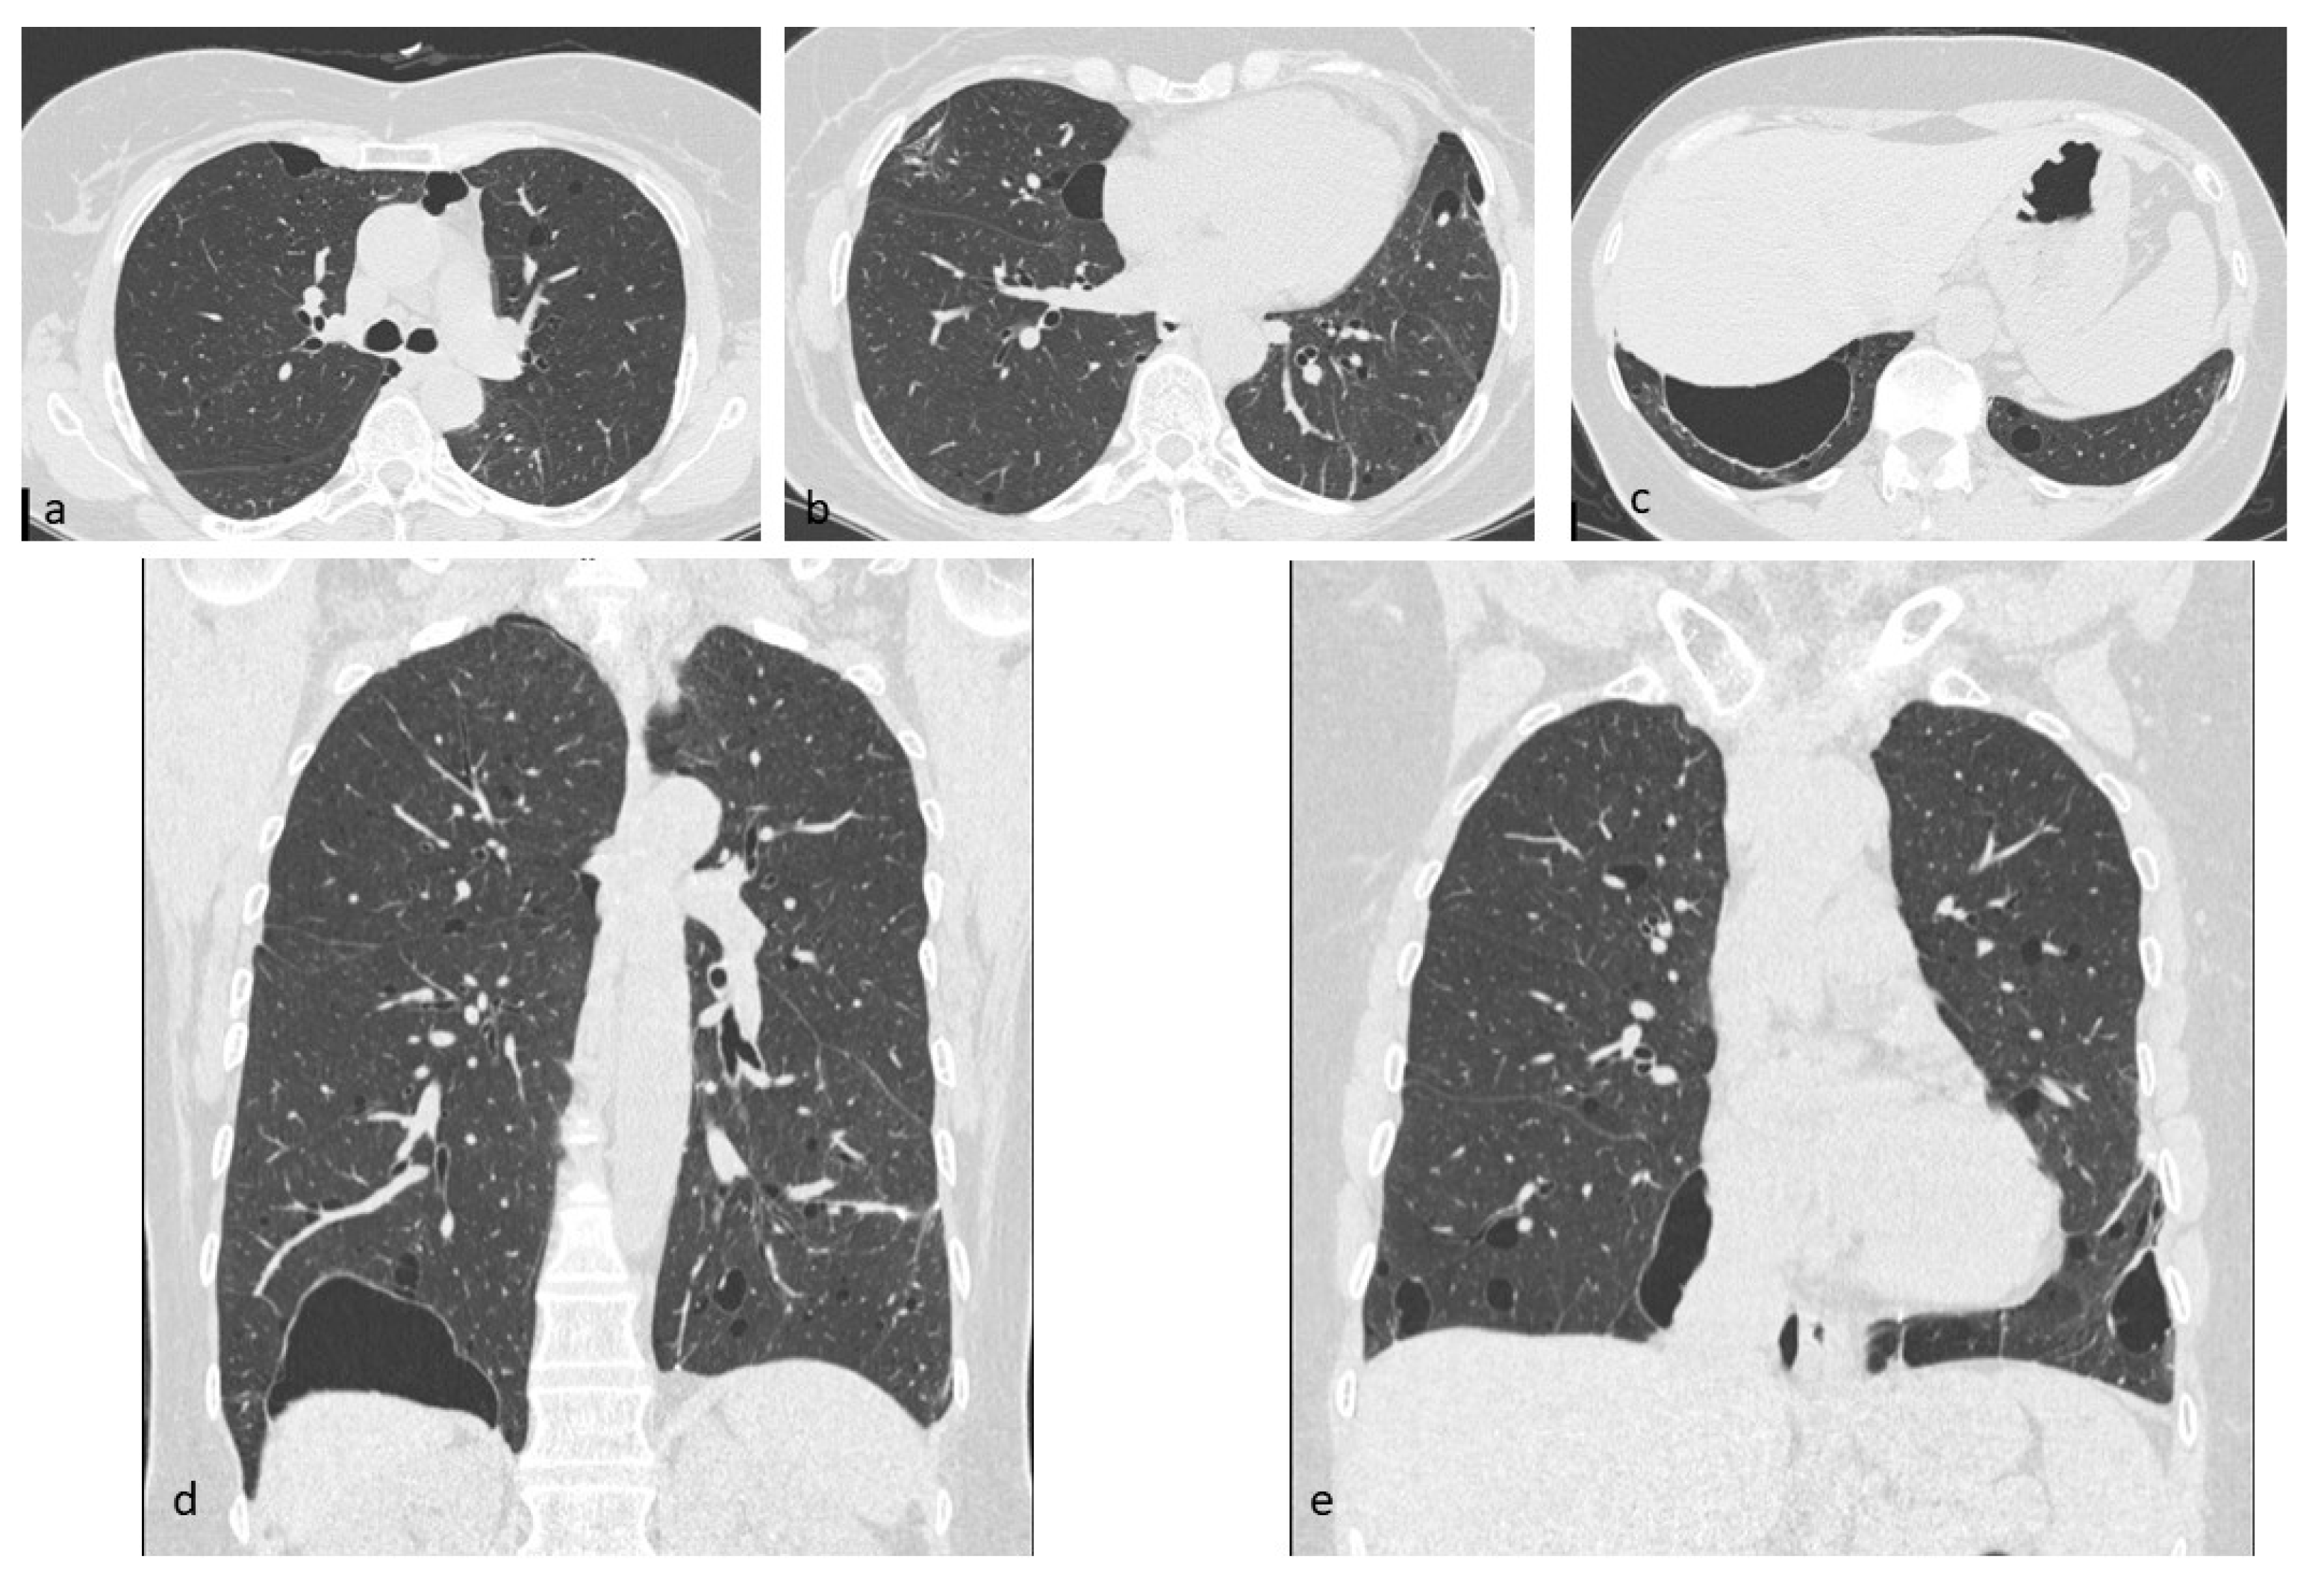

Figure 11. DIP cysts, mostly located in subpleural regions (ad). Multiplanar reconstruction (MPR) in the coronal plane (e). This figure has been partially modified from ECR 2017 / C-2141 Cystic pattern in lung diseases: a simplified HRCT guide based on free-hand drawings, DC Caltabiano, V. Costanzo, L. Mammino, V. Vindigni, S. Torrisi, R. Rosso, LA Mauro, C. Vancheri, S. Palmucci.

The radiological pattern is characterized by parenchymal areas of “ground glass” attenuation [37], having patchy distribution, predominantly depicted in lower lung zones, peripheral and subpleural regions, where micro-cysts, reticular opacities, irregular lines and traction bronchiectasis can be found [38]; honeycombing—which is considered pathognomonic sign of parenchymal fibrosis—is usually absent [39,40]. Cysts occur typically in lower and peripheral lung zones and involve less than 10% of lungs parenchyma [41] (Figure 10 and Figure 11). Other smoke-induced lung diseases, such as centrilobular emphysema and respiratory bronchiolitis—with patchy air trapping on expiratory scans—may be visible and superimposed to DIP alterations. The small air-filled cysts and ground-glass opacities may be stable or disappear spontaneously with smoking cessation or corticosteroid therapy [42]. Surgical lung biopsy is mandatory to confirm the radiological diagnosis, although BAL and a transbronchial lung biopsy may be helpful; in DIP, BAL normally shows an increased number of macrophages, neutrophils, eosinophils and in rare cases lymphocytes.